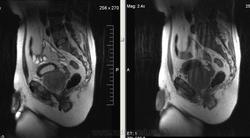

Метастазы рака простаты, кроме измений в позвонках видна сама первичная опухоль и лимфатические узлы (общий и наружный подвздошные слева, ещё один в левой подвздошной ямке).

После добавления томограмм исследования органов малого таза картина стала ещё печальнее...

Да, запустил пациент. До этого были проблемы с мочеиспусканием, рези, болезненность. Лечился самостоятельно от простатита, отмечал временное улучшение.